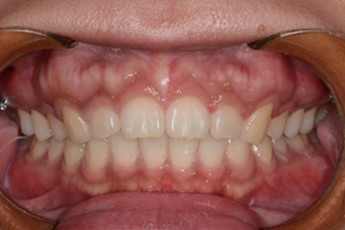

Before

After